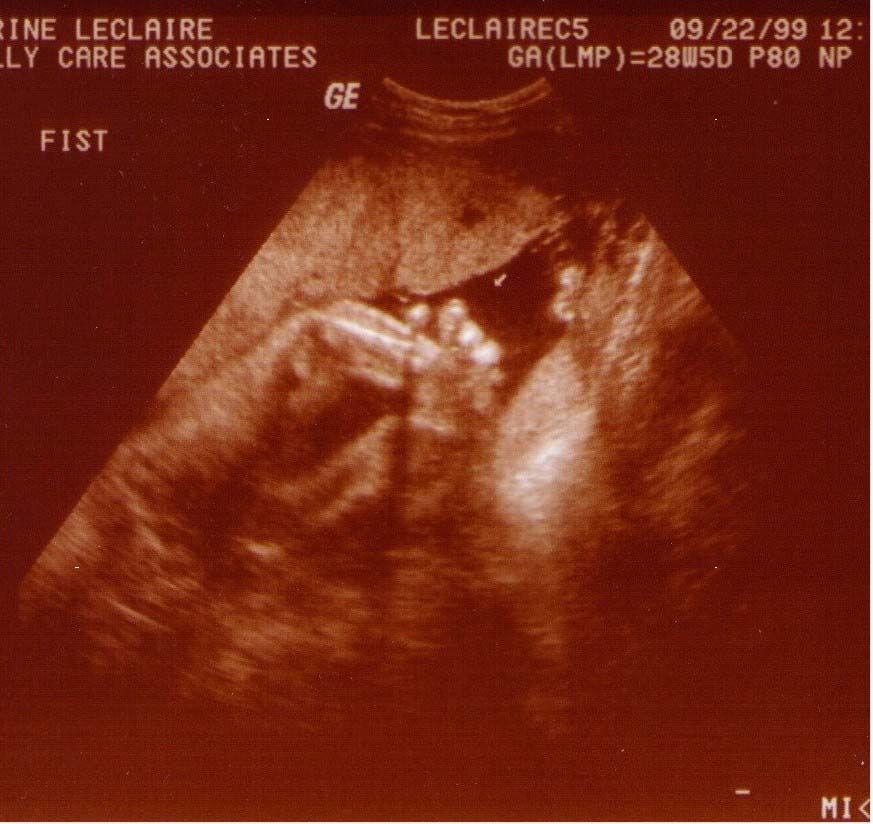

Alexander James LeClaire

Ultrasound Pics!